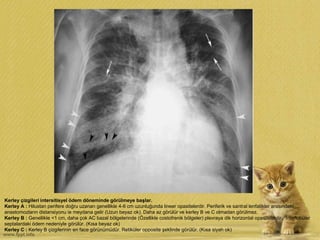

Kerley çizgileri intersitisyel ödem döneminde görülmeye başlar.

Kerley A : Hilustan perifere doğru uzanan genellikle 4-6 cm uzunluğunda lineer opasitelerdir. Periferik ve santral lenfatikler arasındaki

anastomozların distansiyonu ie meydana gelir (Uzun beyaz ok). Daha az görülür ve kerley B ve C olmadan görülmez.

Kerley B : Genellikle <1 cm, daha çok AC bazal bölgelerinde (Özellikle costofrenik bölgeler) plevraya dik horizontal opasitelerdir. İnterlobüler

septalardaki ödem nedeniyle görülür. (Kısa beyaz ok)

Kerley C : Kerley B çizgilerinin en face görünümüdür. Retiküler opposite şeklinde görülür. (Kısa siyah ok)